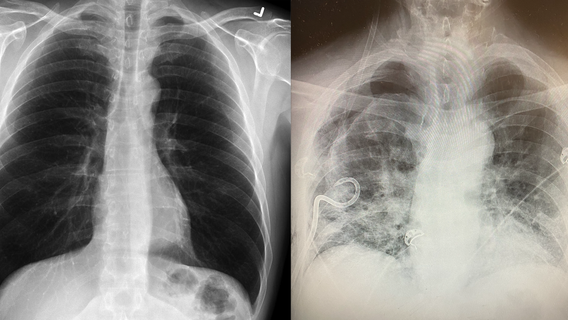

Texas surgeon noticing some post-COVID-19 lungs have more scar tissue than smokers’ lungs

A surgeon in Texas revealed she’s seeing a pattern of lung scarring in some patients who have had COVID-19 that’s worse than what she sees in smokers’ lungs.